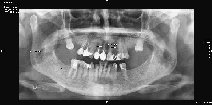

Algunos ejemplos de imágenes digitales

Pulse en las imágenes para ver la ampliación

anciano-fte